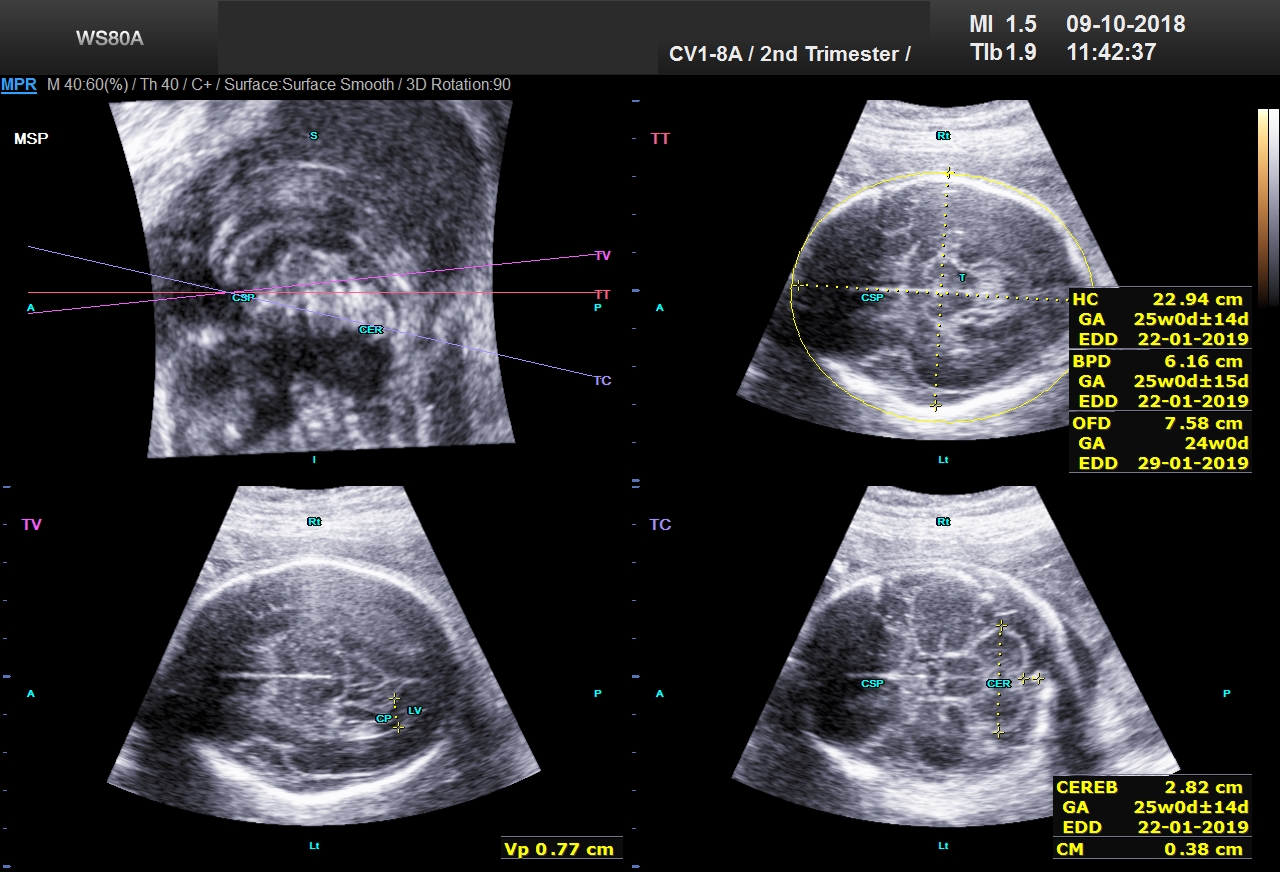

Moja baka je pre nekoliko godina slomila kuk i od tada pa do sada smo je nekoliko puta vodili na skener i ultrazvuk U proseku se cena ultrazvuka kukova krece oko 50 eura u3d4d ultrazvuČni pregled od – 24 nedelje trudnoĆe Ekspertski 4D/3D ultrazvučni pregled od 24 nedelje trudnoće "Anatomskomorfološki pregled sa fetalnom ehokardiografijom" Iako se plod detaljno gleda počev od 12 nedelje trudnoće, ovo je najbolji period za analizu izgleda (morfologije) svih glavnih organskih sistema i spoljašnjeg izgleda bebe3D ultrazvuk lica bebe Poliklinika Dr Kozarić is at Poliklinika Dr Kozarić Sarajevo, Bosnia and Herzegovina ·

U Poliklinici AnaLife rekli su nam da je uvek pravo vreme za 4D ultrazvukIpak, izdvajaju se dva važna termina u 12 nedelji (kontrola na Daunov sindrom) i od do 22 nedelje (prati se anatomija ploda, sa detaljnim pregledom srca) 3D/4D ultrazvuk Olomouc dr Polák už rozebírají maminky na webu eMimino Podívejte se na jejich rady a přidejte do diskuze své zkušenostiOd týdne si můžete natočit DVD s videem a/nebo pořídit 3D fotografii miminka Vyšetření a pořízení snímků trvá zhruba minut Pro maminky je tento typ ultrazvuku nepovinný, cena se pohybuje kolem 1000 Kč Máte pak památku na své těhotenství